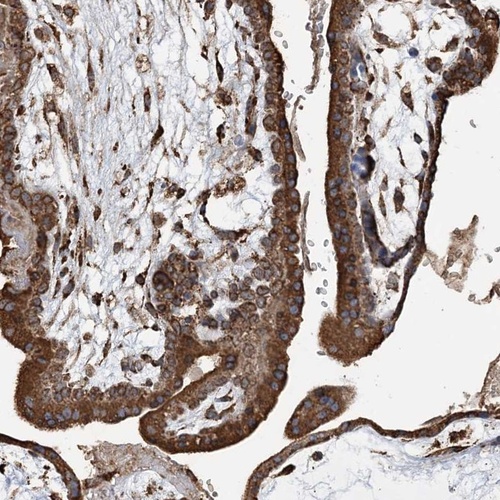

Immunohistochemical staining of human placenta shows strong cytoplasmic positivity in trophoblastic cells.